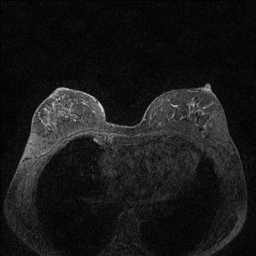

MRI images. The data used in this study are from the DUKE Breast Cancer Dataset [23], a comprehensive single-institutional retrospective collection of 3D MRI scans from over 900 patients with biopsy-confirmed invasive breast cancer at a university hospital. Each study includes a 3D MRI acquired using 1.5T or 3T scanners, from patients in the prone position. On average, each 3D scan consist of 250 2D slices (see Figure 1). For the predictive tasks, the slices are categorized into two groups: those containing breast tumors and those without. Following the approach of [15, 12], we establish a buffer zone between slices containing tumors and those that do not (highlighted in yellow in Figure 1(a)). Images within this buffer zone are excluded from analysis, and the remaining slices are labeled and used for the predictive task.

Vertical orientation. Different from magnetic field strength, which affects the entire image globally, vertical orientation is a local feature that only alters the spatial arrangement of structures within the image. This transformation does not modify the underlying tissue characteristics or signal properties but instead introduces artificial correlations that models may exploit as shortcuts.